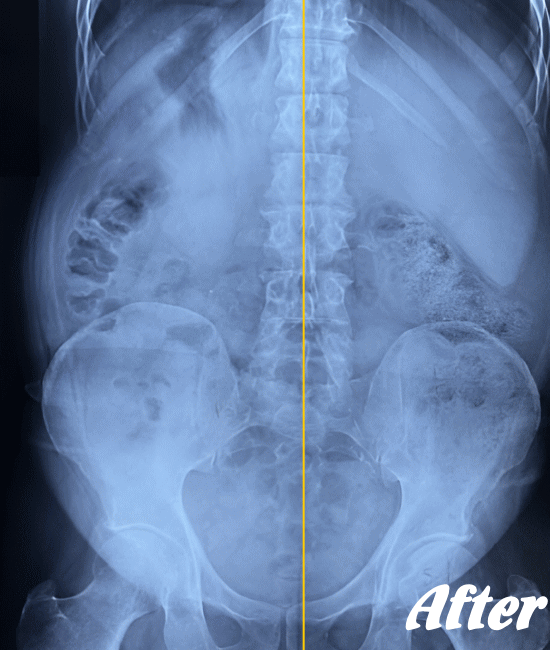

| 施術前(レントゲン) | 施術後(レントゲン) |

|---|---|